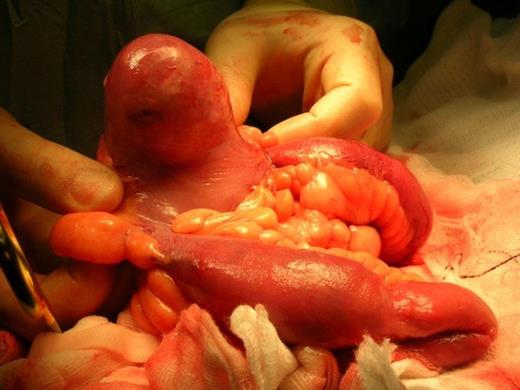

A General Surgeon was invited by the Gynaecologist during laparotomy. Findings were a 20 cm right ovarian cyst and a solid inflammatory 6cm mass within a Meckel's diverticulum with significant cicatrisation of the mesentery (Fig 2). A small bowel resection was therefore done. Pathology report confirmed the presence of a calculi within a Meckel's diverticulum. She made a good recovery and was discharged home 3 days after the operation.

Operative image showing a solid inflammatory 6cm mass within a Meckel's diverticulum